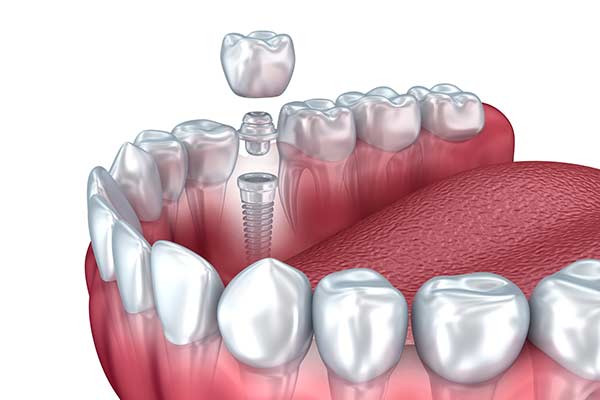

Implant Restorations

Dental implants are composed of three pieces: a small screw made of a biocompatible metal called titanium, an abutment which connects the screw and the final restoration, and the final restoration. The screw, which is placed in the jawbone, acts as a replacement for the tooth root, providing a strong foundation for fixed or removable replacement teeth. The screw begins to fuse with the bone over the course of a few months. After the fusing process, known as osseointegration, the abutment is inserted into the screw to allow for the permanent attachment of the restoration.